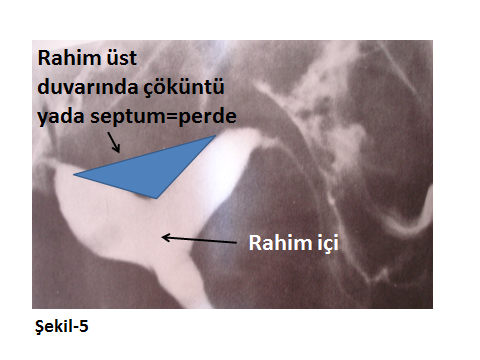

Rahimin normaldeki görünümü üçgen alanına benzeyen bir yapıdır. Bu yapıda doğuştan olan ya da sonradan ortaya çıkabilecek bozukluklar ve bunların dereceleri büyük bir doğrulukla belirlenebilir. Örnek olarak rahim içinde bir Septum yani Perde durumu var ise ufalmış rahim içi boşluğuna bağlı gebe kalamama ya da gebe kalıp tekrarlayan düşükler yaşayan bir kadında sorun Histeroskopik operasyon ile tüme yakın çözülebilmektedir.

Aşağıda farklı HSG görüntüleri ile konu görsel hale getirilmeye çalışılmıştır.

Rahimin doğuştan farklı görüntülerde şekil bozuklukları olabilir. Bunlar derecesine göre, infertiliteye ya da tekrarlayan düşüklere neden olabilirler.

Şekil-5’te normalde üçgen olan rahim içi yapısında var olan çöküklük ya da halk arasında perde olarak da adlandırılan septum görülmektedir. Bu perde (septum), farklı olgularda farklı derinliklerde olabilir. Bu perdeye bağlı olarak da gebeliğin yerleşebileceği normal rahim içi boşluğu farklı darlıklar gösterebilir. Şekil-6,derin bir perde durumunun HSG görüntüsüdür. Bu görüntülerden de fark edileceği gibi rahimin perdeden etkilenmeyen ve beyaz renkte görülen rahim içi alanı çok daralmış olduğu için gebeliğin bu kısıtlı sahalarda büyümesi zor ya da imkansız hale gelecektir.

Bugün bu sorun, çok kısa bir Operatif Histeroskopi yaklaşımı ile düzeltilebilmekte ve kişi normal üçgen rahim içi görünümüne sahip olabilmektedir.